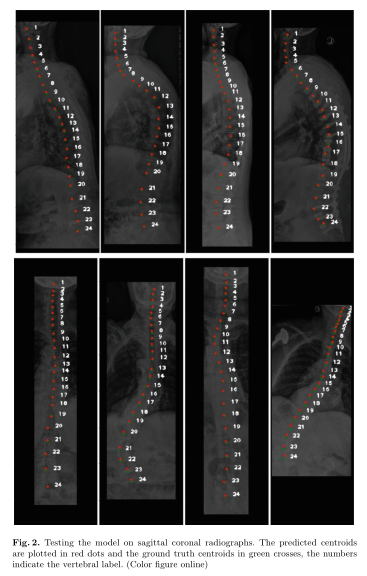

名患者的内部数据集,我们有冠状位和矢状位x线片,我们也有椎心的注释

图片尺寸367x576